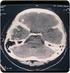

Peranan CT Scan Kepala dalam Diagnosis Nyeri Kepala Kronis

Peranan CT Scan Kepala dalam Diagnosis Nyeri Kepala Kronis Albert Susanto Fakultas Kedokteran Universitas Katolik Atma Jaya, Jakarta, Indonesia ABSTRAK Nyeri kepala kronis mengenai 5% populasi umum dan